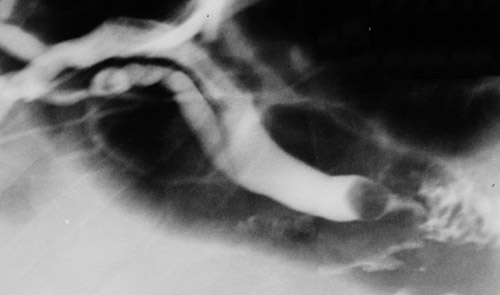

This cholangiogram reveals the outline of a gallstone occluding the distal common bile duct (CBD) near the ampulla. The CBC is dilated. This is choledocholithiasis with biliary tract obstruction.